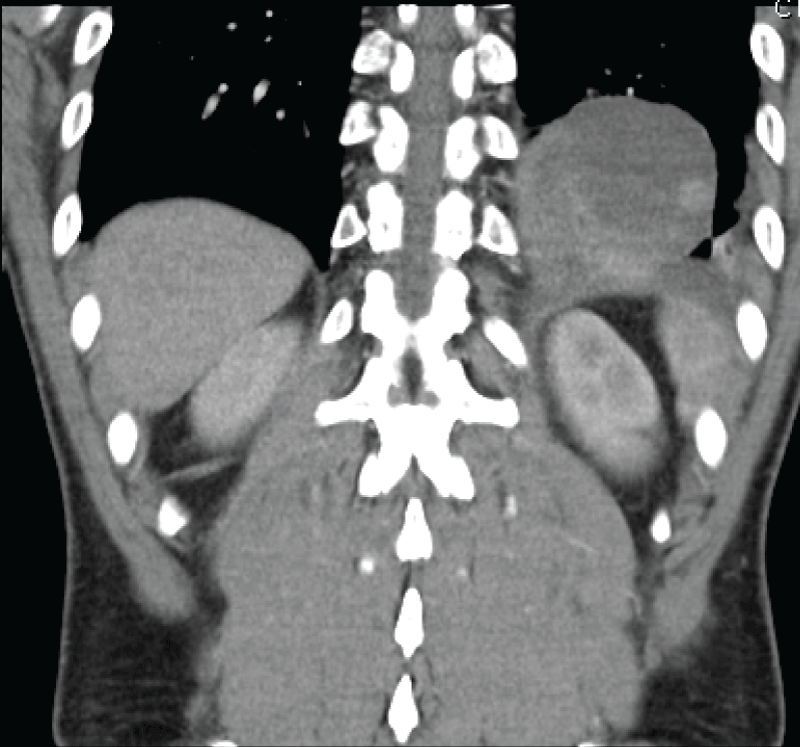

His urinalysis was normal and he had a white blood cell count of twenty, other routine bloods including urea and electrolytes, liver function tests, and lipase were unremarkable however. He went on to have an abdominal CT scan which extended to the lung bases and showed an unusual lesion sitting just above the diaphragm on the left side. Although at first glance similar in appearance to a diaphragmatic, the diaphragm appeared to be intact on the CT scan with no obvious extension of cystic contents below the diaphragm. The lesion was radio dense in appearance and sitting within the posterior basal left lower lobe measuring 94 by 56 mm in diameter. It had low density regions suggestive of fluid or necrosis. There was some associated atelectasis but no pleural effusion. There was no aberrant venous or arterial supply (Figure 1 and Figure 2).